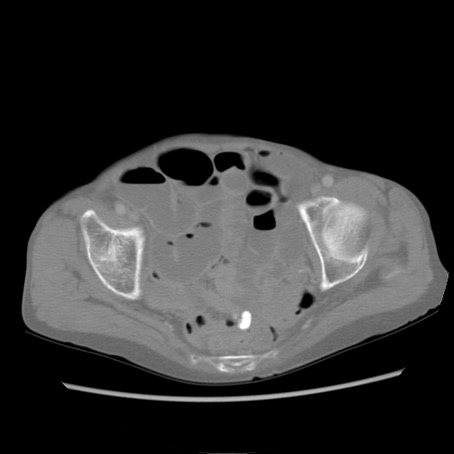

症例25(横断像)

【症例】80歳代女性

【主訴】胸のつかえ感

【現病歴】約9時間前に食後から胸のつかえた感じあり、嘔吐あり、来院。

【既往歴】胃癌(全摘)、胆摘、虫垂炎

【身体所見】心窩部に圧痛あり、反跳痛なし。

【データ】WBC 5700、CRP 0.05